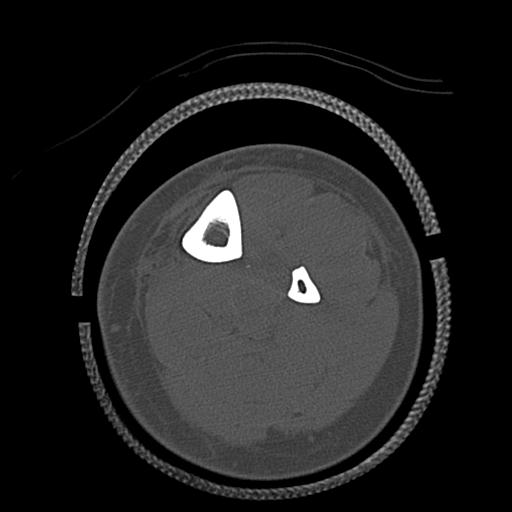

91983 11/16 左膝 2R 11/18 2R 55歳男性 脛骨骨切り術